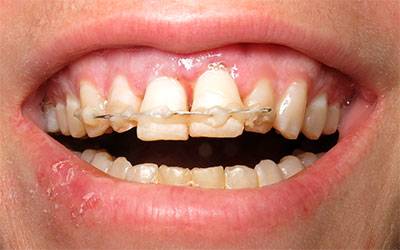

Paciente femenino de 30 años de edad, se presenta en el consultorio en incisivos centrales superiores, férula de alambre y acrílico. El tiempo de evolución es de 6 días después de sufrir una caída, causando la avulsión de sus dientes incisivos centrales, la trataron y colocaron los dientes dos días posterior al accidente.

Dientes Ferulizados

Se toma radiografía periapical con el radiovisiografo, encontrando zona radiolúcida periférica a los dos alvéolos, al retirar la férula los dientes se salen solos en condiciones desfavorables para su reinserción periodontal.